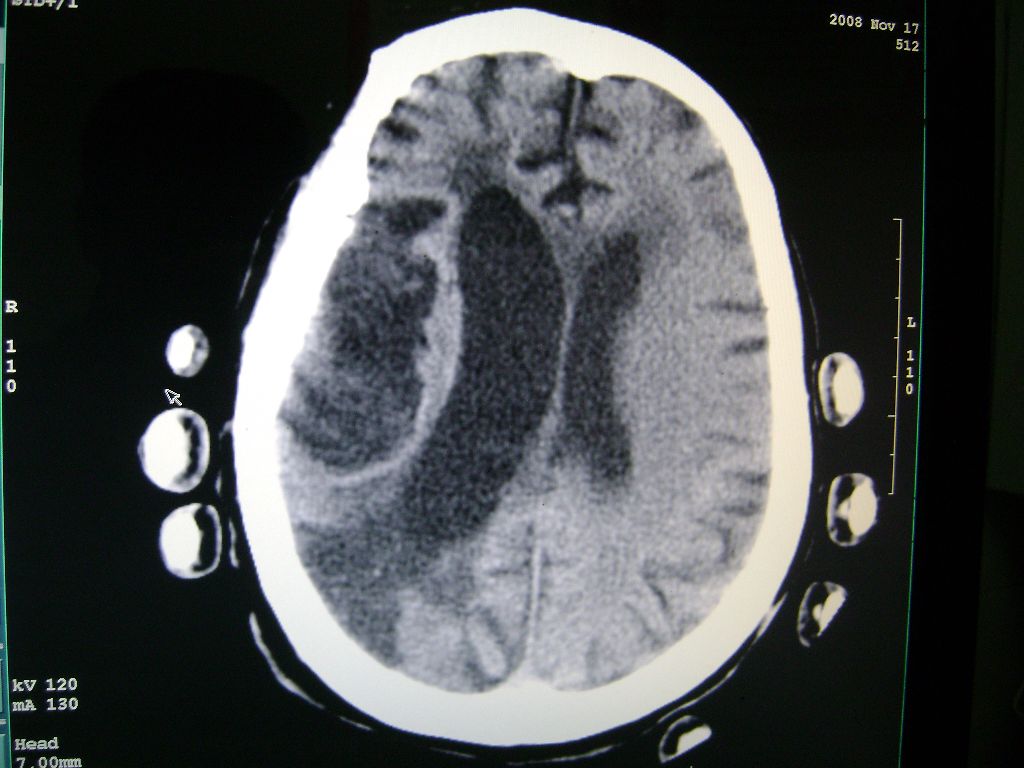

f 77 昏迷不醒

出血性脑梗塞

出血性脑梗塞!

各位根据啥是出血性脑梗塞?????

右侧额颞枕顶叶脑软化灶,脑萎缩,大脑中动脉壁钙化。

右脑软化灶,考虑再次梗塞,高密度灶出血?钙化?。。。量ct值,改窗宽,位

右脑软化灶,考虑再次梗塞,右顶叶高密度影不像是出血,密度很高,建议量ct值!

右侧半球陈旧性卒中,不除外伴有新病灶,左额叶梗塞,双侧大脑中动脉钙斑

右侧额颞枕顶叶脑软化灶,脑萎缩,大脑中动脉壁钙化。不支持出血(密度高,边界清且局限)顶枕区似有新发梗塞,建议核磁

1)右侧额颞枕顶叶脑软化灶;其内高密度影,多为钙化灶。2)脑萎缩。3)大脑中动脉钙化。

再次脑梗死,右侧额颞枕顶叶脑软化灶,高密度考虑钙化

右侧陈旧脑梗塞伴脑萎缩。脑内点状钙化。大脑中动脉壁钙化灶。无出血灶。

1)右侧额颞枕顶叶脑软化灶并钙化灶可能。2)脑萎缩。3)大脑中动脉钙化。 -